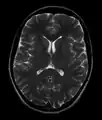

- T2-weighted (T2W) images: CSF is light, but fat (and thus white matter) is darker than with T1. T2-weighted images are useful for visualizing pathology.[26]

Normal axial T2-weighted MR image of the brain